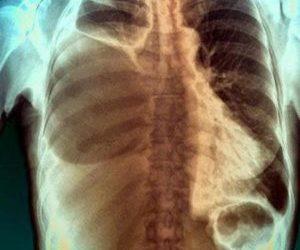

Обнаружение симптомов заболевания служит поводом для немедленного обращения к врачу. Для установления точного диагноза могут быть полезны следующие методы обследования:

- физикальное обследование;

- рентгенография;

- ультразвуковое исследование плевральной полости;